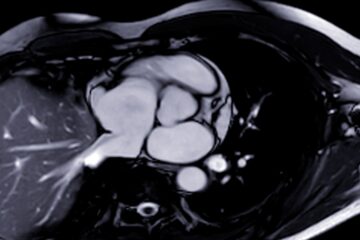

Galio skenavimas yra vaizdinis tyrimas, padedantis gydytojams nustatyti vėžį, infekcijas ar uždegimą organizme. Procedūros metu į kraujotaką suleidžiama mažas kiekis radioaktyvios medžiagos. Ši medžiaga, vadinama galiu, keliauja į kūno vietas, kuriose yra uždegimas ar infekcija. Speciali kamera užfiksuoja detalius šių vietų vaizdus, padėdama gydytojams nustatyti problemas.

- Jūs gulėsite ant nugaros ant skenavimo stalo. Speciali kamera nustato, kur organizme susikaupė galis.